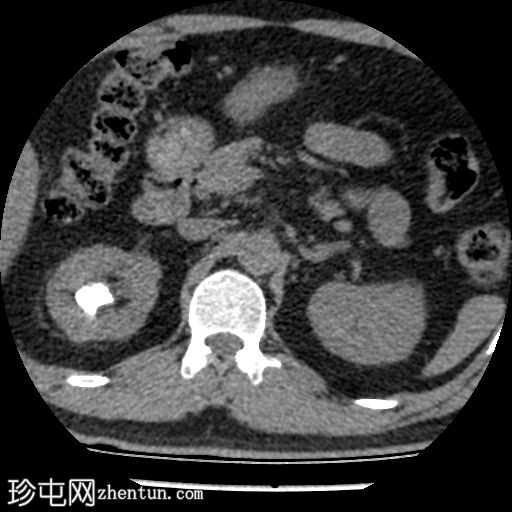

轴位(非增强)

右肾上盏内可见一中等大小的结石,大小约为16 x 13 x 15 mm。右肾中盏内可见一小结石,大小约为4 x 2 mm。右肾下盏内可见另一小结石(过小无法测量)。未见肾盂肾盏扩张。

非增强 CT KUB 显示右肾多发结石,其中上肾盏结石较大,大小为 16 x 13 x 15 mm,密度较高(平均约 1060 HU),符合钙结石的特征。中肾盏和下肾盏可见其他较小的结石。

肾盂肾盏系统未见扩张,提示无梗阻性病变。该发现与患者反复腰痛的病史相符,腰痛可能与结石移位有关,而非当前存在梗阻。